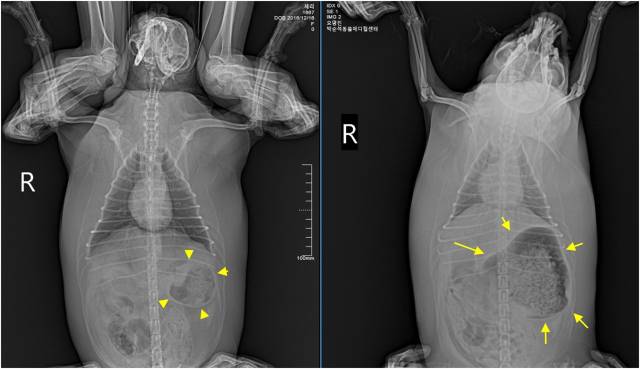

뭉치는 2시간 이상 집중 산소 공급을 받고 나서야 호흡이 안정됐다. 체온도 39℃ 이하로 내려왔다. 미뤄 두었던 X-Ray 검사가 실시됐다. 그런데 상황이 특이했다. 환자견의 흉부 가 압박되어 폐 용적이 줄어 있었다. 반면에 배는 엄청 팽대되어 있었다. 위내 범상치 않은 음식물이 공기와 함께 가득차 있었으며 소장까지 공기가 가득 차 있었다. 팽대된 복강이 흉부를 짓누르는 상황이었다.